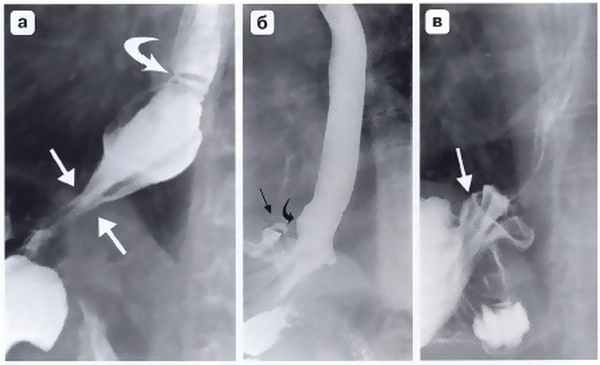

Другим важным и довольно частым осложнением операции фундопликации по Ниссену является соскальзывание кардиального отдела и дна желудка с терминальным отделом пищевода относительно манжетки (рис. 4, б). Как правило, причиной этому служит прорезывание швов между манжеткой и пищеводом. Ушивание ножек диафрагмы при укорочении пищевода и фиксация к ним антирефлюксной манжетки также приводят к «соскальзыванию», поскольку пищевод, сократившись после операции, втянет за собой кардию вместе с расправленной манжетой в заднее средостение. Рентгенологически это выглядит в виде феномена «песочных часов», когда одна часть манжетки находится выше диафрагмы, а другая — ниже (рис. 5). Осложнение сопровождается выраженной дисфагией, регургитацией и изжогой, что, безусловно, требует повторной корригирующей операции. Частой ошибкой при использовании эндоскопической техники является использование тела или даже антрального отдела желудка при формировании антирефлюксной манжетки (см. рис. 4, в). Если короткие желудочные сосуды не пересечены, хирург вынужден использовать при фундопликации на 360° не дно желудка, а переднюю его стенку. Все это ведет к перекруту, выраженной деформации желудка, который, по понятным причинам, не способен выполнять антирефлюксную функцию и является основной причиной высокой частоты послеоперационных осложнений в виде дисфагии (11-54%) при этом способе операции.

Рис. 4. Осложнения после фундопликации по Ниссену: а — полный разворот манжетки при прорезывании швов; б — соскальзывание кардиального отдела и дна желудка с терминальным отделом пищевода относительно манжетки; в — сформированная вокруг кардиального отдела желудка манжетка; г — втягивание антирефлюксной манжетки в заднее средостение при укорочении пищевода (Черноусов А.Ф. и др.)

Рис. 5. Рентгенограмма. «Соскользнувшая» фундопликационная манжетка: а - соскользнувшая манжетка расположена ниже уровня диафрагмы и сдавливает кардиальный отдел желудка, пищеводно-желудочный переход находится над диафрагмой; б, в - при двойном контрастировании отчетливо видны складки слизистой желудка внутри соскользнувшей манжетки с образованием дивертикулоподобной деформации (подобный дивертикул нередко становится источником желудочно-пищеводного рефлюкса и прогрессирующего рефлюкс-эзофагита) (Черноусов А.Ф. и др.)